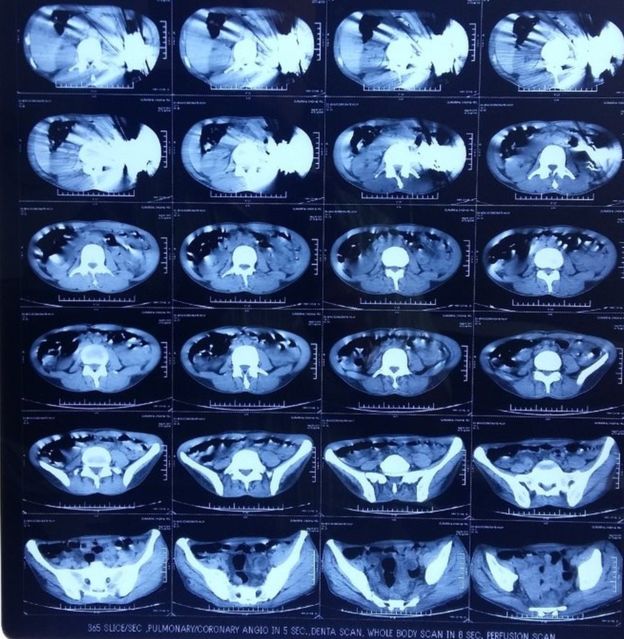

“在内镜检查时,我们在他腹部看到了一个大家伙,”他说,“我们最初以为那是一个肿瘤或是其他癌变生长物,那不像是我们医生此前见过的任何东西。”

美联社称,被取出的刀有些处于折叠状态,有些刀刃则暴露在外,最长可达7英寸(约合18厘米)。

医院方面称,手术医师最初取出了28把刀,但在进行进一步检查后又发现了另外12把。马尔霍特拉说,手术过程中男子大出血,因为刀已经割裂了胃壁。